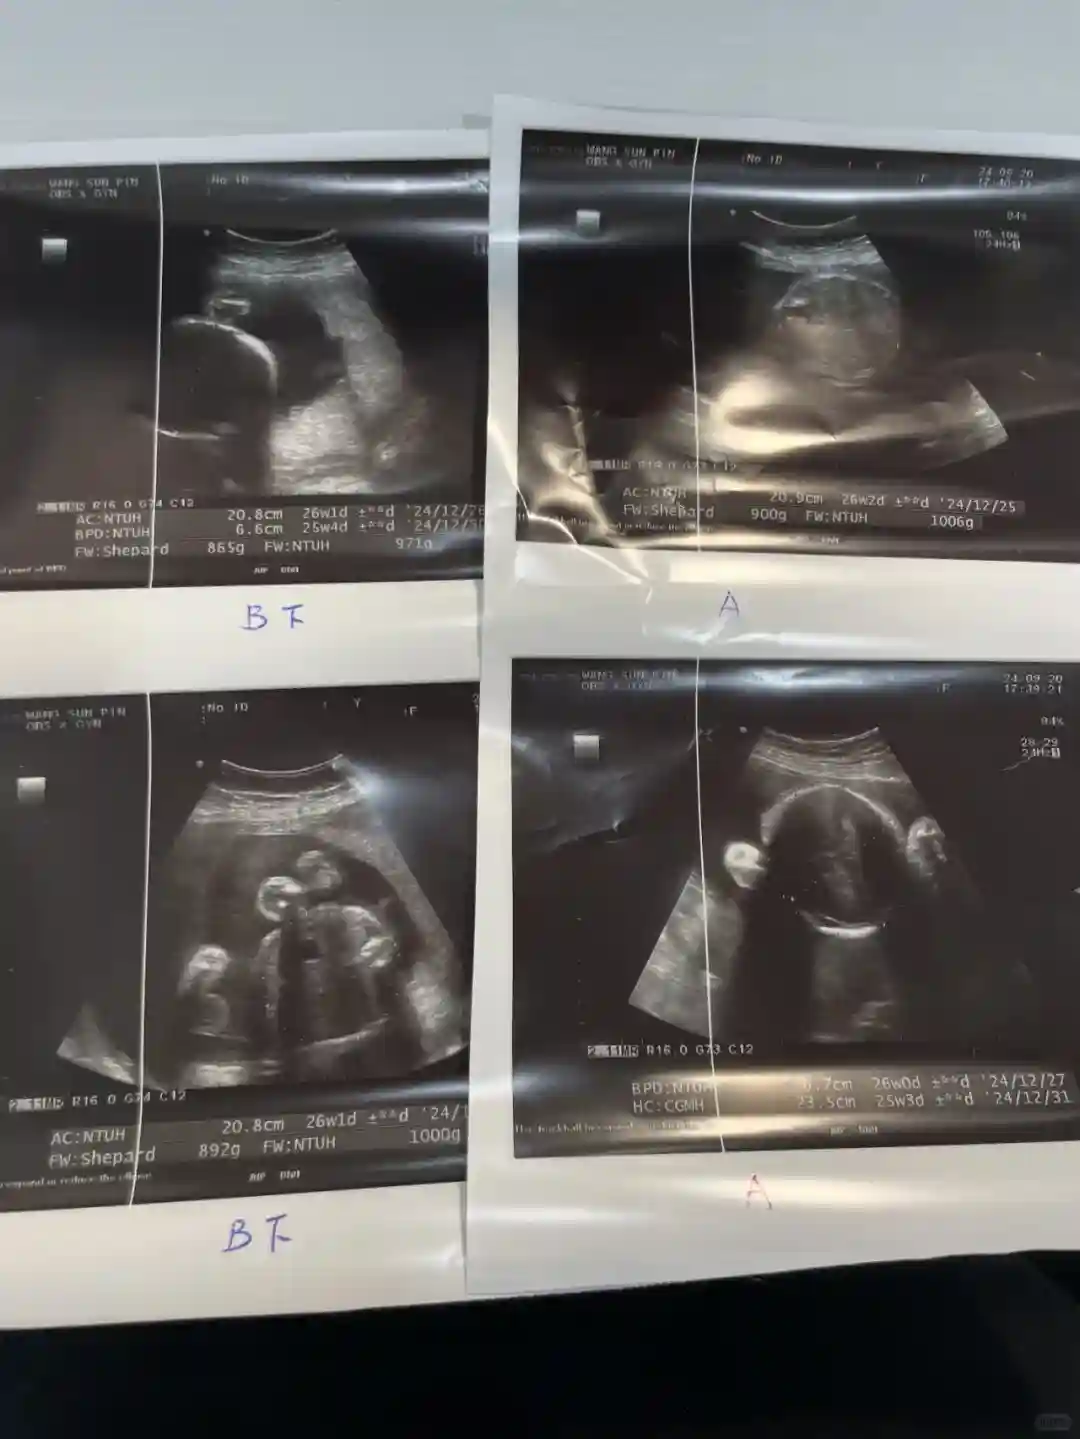

两个儿子现在分别是 1000g 和 961g。 妈妈正在努力获取营养, 你也认真对待成长, 难怪我今天💕💕觉得自己动弹不得 婴儿总是在移动, 大叔医生说你们真是动👍起来了(这是赞美啊!大今天我终于知道为什么我会一直处于尿路炎症中并且已经有一段时间了。 我添加了很多浆果和有益细菌等。 加上醫生開的藥, 一次更好,再一次, 在我怀孕之前,我真的没有尿路炎症。医生说:因为双宝越来越大,压在我妈妈的膀胱上,所以马桶不顺,很容易变成感染!所以, 终于知道为什么是很多平静!接下来是吃药防止发炎, 高度警觉的掌声, 我真心認為準媽媽們, 在你真的不舒服的地方不要忍受。 马上回到诊所就好了!我從16-27週都是週週超音波, 谢谢你🥹遇到了好医生 💕💕 生活真的很贵!有没有像我这样的妈妈? 您是否也😷一直对尿路感到不舒服#同卵雙胞胎 这本来应该是一次为期两周的检查。